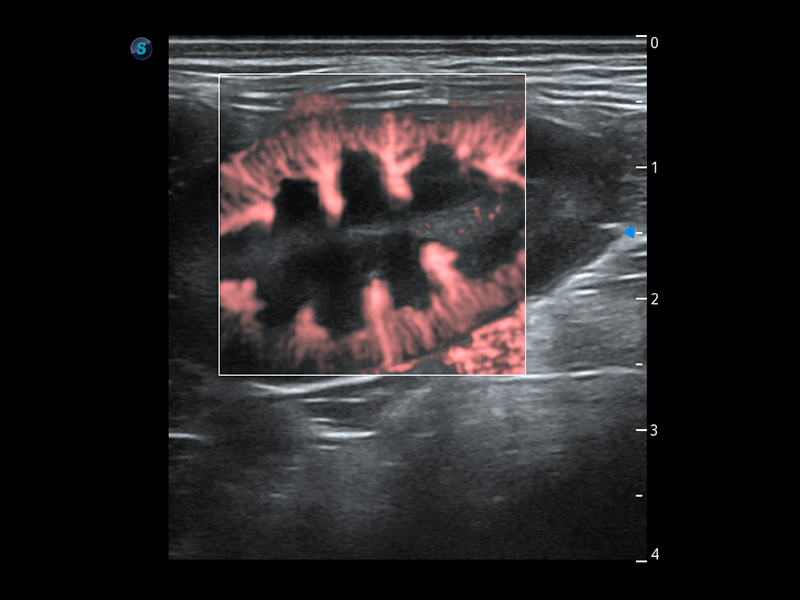

ProPet 60 作為一款高端臺(tái)式動(dòng)物超聲設(shè)備,為動(dòng)物醫(yī)生的日常診斷提供了一系列貼合動(dòng)物臨床需求、解決臨床實(shí)際問(wèn)題的高級(jí)成像功能。憑借全系列高清探頭,滿足醫(yī)生對(duì)腹部、心臟、生殖、淺表、肌骨等成像的所有需求,切實(shí)幫助您提升檢查效率,提高診斷信心。